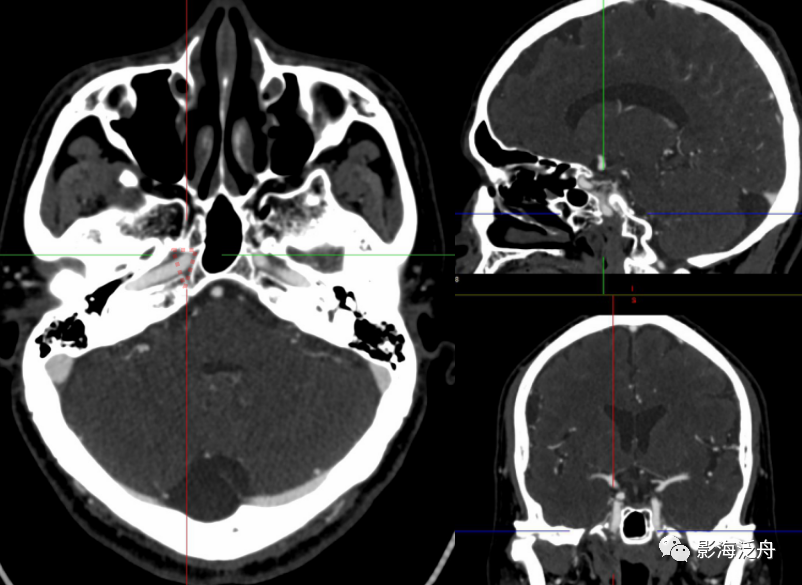

事实上关于颈内动脉分段的方法有很多种,本文重点介绍我们平时工作中最常用的一种分段方法,该分段由Bouthillier教授于1996年提出并沿用至今。

分段的全面展示如上图所示,包括7段:C1颈段(Cervical segement)C2岩段(Petrous segment)C3破裂孔段(Lacerum segment)C4海绵窦段(Cavenous segement)C5床突段(Clinic segment)C6眼段(OPhtalmic segement)C7交通段(Communicating segment)

10e3e41d44ed8f6dc6134752da5f4dad.png

C1段(颈段),无殊。

9a7ee0e6c9f6991ef27798793aaf008c.png

cdcc78636ae1f730e519b1bfa078ce0a.png

C2段(岩段)走行于颅底颈动脉管内,骨性管道起到限制颈内动脉颅外段向颅内的继续撕裂。C2段可细分为垂直段与水平段,如上图所示。